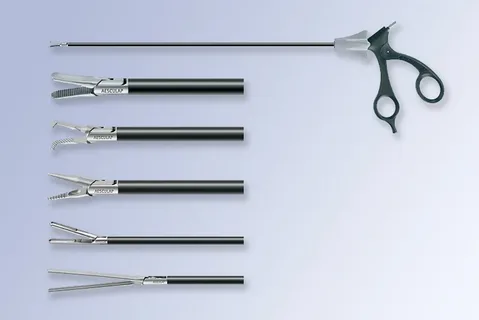

Robotic and Minimally Invasive Surgical Methods

Surgical oncology has benefited significantly from robotic-assisted and minimally invasive techniques. These approaches allow surgeons to operate with enhanced visual clarity and controlled movement. Smaller incisions result in reduced blood loss and shorter hospital stays. Robotic systems support complex procedures in which precision directly affects recovery and function. Faster healing also enables patients to proceed with chemotherapy or radiation without unnecessary delays. Surgical innovation continues to play a key role in improving outcomes within cancer treatment in Mumbai.